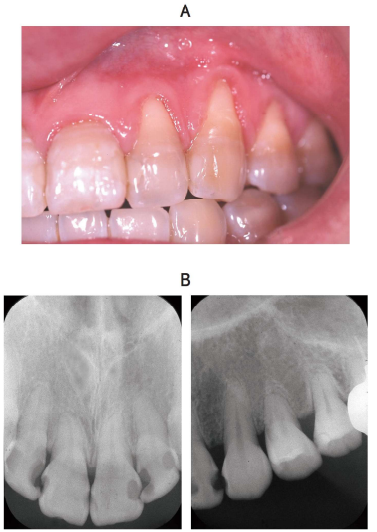

80 歳の男性。下顎前歯部の動揺を主訴として来院した。 5 か月前から自覚し、1 か月前から動揺が強くなり、前歯で咬みづらくなったがそのままにしていたという。初診時の口腔内写真(別冊No. 26A)とエックス線画像(別冊No. 26B)を別に示す。歯周組織検査結果の一部を表に示す。

適切な対応はどれか。 3 つ選べ。

解答:abc

解説:

ポケット:深くはないが出血してる。動揺はある。

骨吸収:前歯に水平性の骨吸収

a 咬合調整:動揺しているので当たらないようにする。

b 暫間固定:動揺を落ち着かせる。

c 口腔清掃指導:全体的に出血しているのでもう少しキレイに磨こう。

d オーラルスクリーンの使用:唇を閉鎖するための器具はいらない。

e 局所薬物配送システム〈LDDS〉:そこまでの炎症ではない。